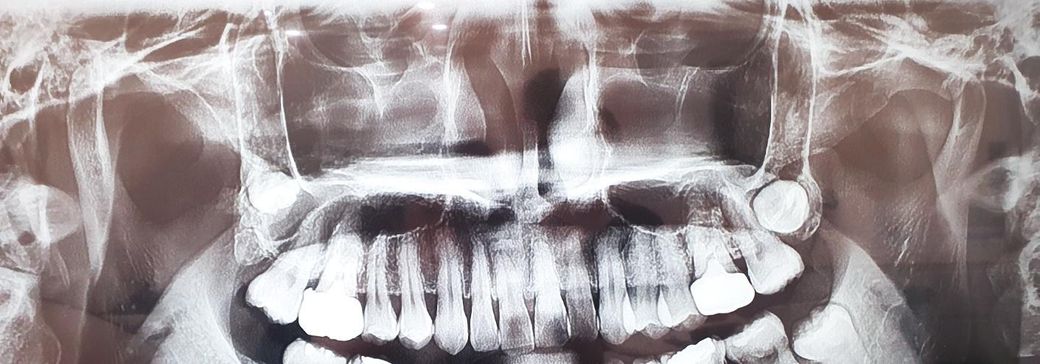

턱뼈 길이 모양 비정상 스플린트 효과.

양쪽 턱뼈 길이도 다르고 한쪽은 모양도 유난히 비정상적이고 그래서 비대칭도 심한데 양쪽 턱도 한번씩 불편하고해서 스플린트를 해봐야하나 고민중이예요

턱뼈가 저런상태여도 스플린트하면 통증이 좀 나아질까요? 턱뼈 위치는 양쪽 다 정상에 있는건가요?

1. 하악과두의 위치는 특별히 문제는 없어보입니다.

2. 턱관절 불편 통증 시 해볼 수 있는 비수술적 치료로 장치치료, 물리치료, 약물치료가 있고 스플린트로 질문자분의 증상도 개선의 여지가 있습니다

턱뼈의 모양은 방사선 사진을 찍을 때의 각도 등에 따라서 다르게 보일 수 있습니다. 턱관절 질환이 있다면 턱관절 질환을 치료하는 것이 좋으며 경우에 따라서는 스플린트 치료가 필요한 경우도 있습니다.

스플린트를 하게 되면 턱관절의 통증을 줄이는 데에는 도움이 될 것이지만 비대칭이 개선되진 않습니다.

파노라마사진으로는 턱관절을 정확히 판단하는건 어렵습니다.대학병원 구강내과를 가셔서 턱관절 CT촬영및 통증 검진후 스플린트 상담을 받아보시는게 좋을것같습니다.

현재 사진으로는 턱뼈 길이나 비대칭 여부를 알 수 없습니다. 파노라마 사진은 3차원적인 자료를 2차원으로 옮겨 놓은 것으로 치조골 및 주변 조직의 왜곡이 심합니다. 따라서 해당 사진으로 턱뼈 길이나 비대칭 여부를 판단하지 않으며 사진으로 정확히 알 수 없습니다.